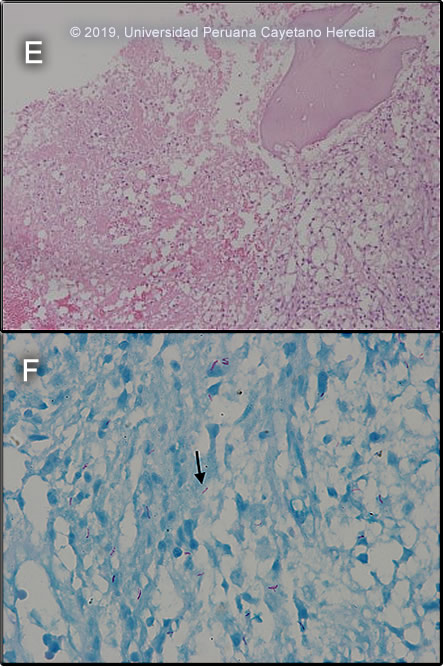

![]() Discussion: A bone marrow biopsy and aspirate from iliac crest showed inflammatory necrosis with histiocytes and lymphocytes without epithelioid differentiation. No evidence of multinucleated giant cells or malignant cells. (Image E) The bone marrow aspirate AFB stain was positive (Image F), and a Gene Xpert MTB-RIF test showed presence of mycobacterial DNA (amplification of IS 6110 and IS 1081) without rifampin resistance (lack of rpoB gene mutations), culture and drug susceptibility testing is pending. Tuberculosis is caused by 3 related organisms Mycobacterium tuberculosis, M. africanum, and M. bovis. Of these, M. tuberculosis is by far the most common [Reichman LB, Hershfield ES, editors. Tuberculosis: a comprehensive international approach. New York: Marcel Dekker; 1993]. The initial route of entry of M. tuberculosis is usually the respiratory tract, followed by hematogenous dissemination. Secondary hematogenous seeding can occur from a silent focus elsewhere in the body (eg gut, kidney). Skeletal tuberculosis is thought to result from hematogenous dissemination from a primary site and occurs 6 months to 3 years after primary infection; but cases associated with relapsing disease have been reported. Skeletal TB accounts for 10 – 35% of all TB cases with 50% being spinal TB (Pott’s disease). Sacroiliac involvement with radiological abnormalities is uncommon accounting only for 1-5% [J Bone Joint Surg Br. 1997 Jul;79(4):562-6] In classical TB spondylitis, the disease process begins in a lumbar intervertebral disc and spreads via the anterior ligament to affect the anterior aspects of the adjacent vertebrae. Destruction of the anterior endplates ensues with anterior collapse leading to a wedge deformity. In our patient, there was compromise of the SI joint with spondylitis and multiple vertebral bodies compromise. Interestingly no compromise of endplates (anterior or posterior) were appreciated which could be related to the related immunosuppression due to HIV infection. However, in some series, a high proportion of patients with bony disease had posterior element involvement (28%), all in association with vertebral body disease. [Spinal Tuberculosis in HIV-Prevalent Setting CID 2018:67]. Sacroiliac tuberculosis is often associated with tuberculous lesions elsewhere, and it primarily originates from a tuberculous psoas abscess or tuberculous spondylitis [see Clin Orthop Relat Res. 1999 Jan;(358):215-22]. No psoas abscess was associated in our case, but as seen on MRI (Image E) likely his SI joint involvement originated from the related spondylitis. Given the broad differential diagnosis and the degree of compromise of the SI joint bone marrow aspirate and biopsy were obtained for cultures for mycobacteria but also for other common bacterial pathogens including Brucella and typhoid. TB sacroiliitis /spondylitis should be differentiated from other infectious disease processes such as pyogenic causes (staphylococcal, gonococcal), typhoid and brucellosis. Non-infectious causes include degenerative and post-traumatic arthritis; inflammatory diseases such as sero-negative spondyloarthropathies, ankylosing spondylitis, psoriatic arthritis, Reiter’s and Behcet’s syndrome, inflammatory bowel disease, rheumatoid arthritis and systemic lupus erythematosus; familial Mediterranean fever with multisystem involvement including arthritis; osteitis condensans ilii; metabolic conditions such as gout pseudogout and hyperparathyroidism; tumors and tumorlike conditions, and pigmented villonodular synovitis [Resnick D, Niwayama G (1995) Osteomyelitis, septic arthritis, and soft tissue infection: organisms. In: Resnick D (ed.) Diagnosis of bone and joint disorders. Saunders, Philadelphia, pp 2461–2485]. Complete destruction of vertebral bodies and the intervertebral disc is seen almost exclusively in infectious processes. Salmonella infection or staphylococcal infections may cause spondylitis and paravertebral abscesses, but concomitant high fever, leukocytosis, and significant systemic illness would be seen. A common feature in these infections is bone remodeling and new bone formation, which was not observed in this patient. Brucellosis, another bacterial cause of sacroiliitis, is endemic in Peru. Spinal brucellosis typically affects the lumbar spine with both lytic and blastic lesions [see Gorgas Case 2001-02]. Malignancy is limited to the vertebral bodies without impinging the intervertebral disc.< The first and second sacral roots pass near the SI joints, with the joint capsule being bordered by the psoas muscle in front and the gluteal and pyriformis muscles behind. Depending on the capsular region involved in the arthritis, the pain may be gluteal or inguinal, mimicking damage to the hip. Frequently, mycobacterial infections of the sacroiliac joint may present as a psoas abscess, and may not be diagnosed until spontaneous drainage occurs in the groin [see Am J Med. 1988 Mar;84(3 Pt 2):622-8]. Buttock pain is invariably present in tuberculous sacroiliitis (as in our patient). The sacroiliac pain can be referred to the groin, posterior thigh, and occasionally below the knee, mimicking pain originating from the lumbar spine, the hip and the lower abdominal quadrant [see J Bone Joint Surg [Am] 58(6):845–849]. There may be signs of femoral or sciatic nerve root irritation if the distended anterior joint capsule comes in contact with the lumbosacral plexus. Confirmed diagnosis of TB spondylitis and sacroiliitis in developing countries is difficult, due to limitations in obtaining representative samples and on the low bacterial load associated with these infections. Diagnostic aspiration or biopsy of the sacro-iliac joint is appropriate when there is minimal bone destruction or at early stages of disease. Bone marrow culture and biopsy is extremely helpful as it will help differentiate from other etiologies (ie. brucellosis, typhoid). Molecular methods, such as the Gene Xpert MTB/RIF allow for faster diagnosis and prompt initiation of treatment. Samples such as bone marrow or urine are appropriate and indicate the disseminated nature of the infection [see BMC Infect Dis 2016;16:514]. Treatment of TB sacroilitis is with standard regimens of anti-TB drugs for at least 9 - 12 months, but more prolonged therapy is recommended in patients with extensive bone destruction and vertebral and paravertebral extension. In TB sacroiliitis, controversy exists as to the need for early surgery. In some series, healing of the infection was accelerated when debridement was done prior to treatment initiation. None of the studies of shorter course chemotherapy have included enough patients with skeletal disease to make any conclusions possible. Patients with acute neurologic deficits within the previous 12-24 hours that suggest extension of disease into the spinal canal should definitely have surgery. Steroids should be considered for very severe paraplegia, especially in the acute stage. Recommendations for a surgical procedure in TB spondylitis include (1)Patients with spinal disease and advanced neurological deficits, (2)Patients with spinal disease and worsening neurological deficits progressing while on appropriate therapy, (3)Patients with spinal disease and kyphosis >40 degrees at the time of presentation and (4)Patients with a cold abscess in the chest wall. Our patient was started on the standard 4-drug initiation regimen of daily isoniazide, rifampin, ethambutol, and pyrazinamide in addition to prednisone for the neurological compromise. Surgical evaluation and discussion of approaches to further joint stabilization are ongoing. ARV treatment was initiated with EFV/TDF/FTC. |